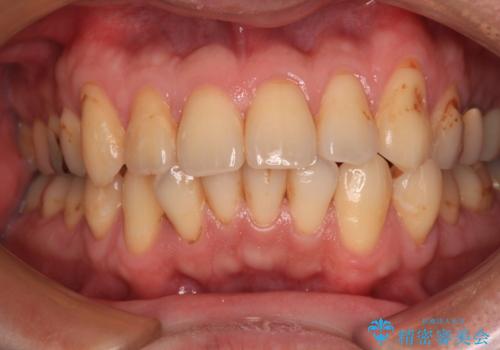

前歯をきれいにしたい オールセラミッククラウンにによる補綴